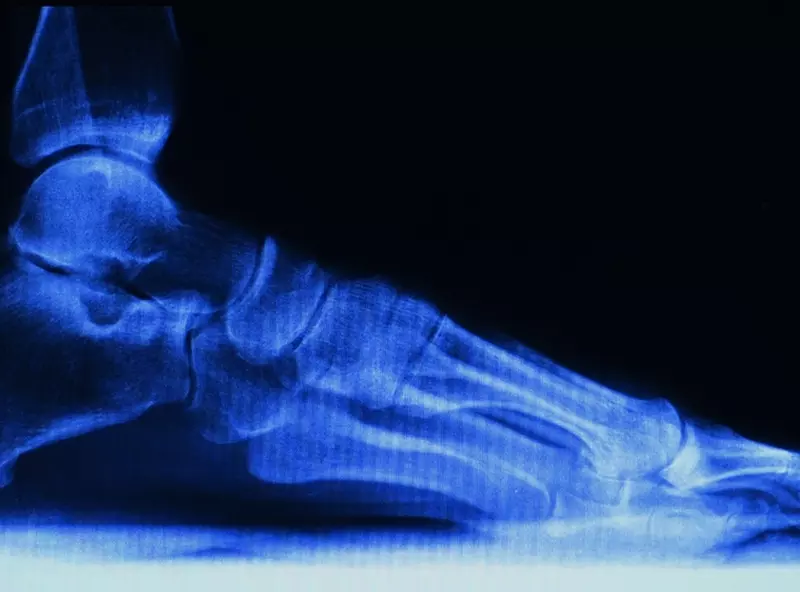

Staw kolanowy jest największym stawem w organizmie człowieka. Jego specyficzna budowa, a także długa dźwignia sprzyjają powstawaniu kontuzji, dlatego jest to jedna z najczęściej uszkadzanych struktur. Urazy stawu kolanowego stanowią prawie 70% wszystkich urazów sportowych [1–3].

Większość urazów kolana dotyczy aparatu więzadłowego. W obrębie udowo-piszczelowym uszkodzeniom ulegają łąkotki, więzadła poboczne piszczelowe oraz chrząstka stawowa. W obrębie rzepkowo-udowym przy mechanizmach powodujących zwiększenie przyparcia rzepki do powierzchni rzepkowej uda występują zespoły bocznego przyparcia rzepki, przeciążeniowe rozmiękanie chrząstki oraz nawykowe podwichnięcia i zwichnięcia rzepki. Urazy te stwierdza się przeważnie w kolanach z wadami rozwojowymi oraz w przypadku nieprawidłowości osi kolana w kierunku koślawości [5].